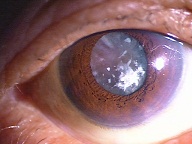

今日いらした24歳女性の症例です。

強い充血を認めます。写真の右側は、はやり目に特徴的な後遺症で、黒目(角膜)が濁っている写真です。もう少し分かりやすい、ヒドイ症例の写真を出したいのですが、ヒドイ症例は第一診察室には入らないようにしていただいたり、写真をとるなどの、余分な時間を少しでも省いて診療を行い、院内感染を予防する必要があり、なかなか難しいのです。